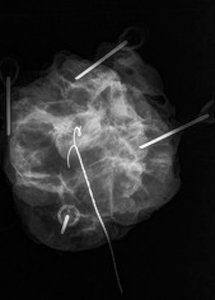

Präoperative Drahtmarkierung und Präparateradiografie

Sonografisch nicht oder nur erschwert darstellbare Befunde (z.B. Mikroverkalkungen der Brust) werden vor der Operation mit einem Draht markiert über den der Operateur die Veränderung leichter und mit geringem Gewebeschaden lokalisieren kann. Der Draht wird unter mammografischer Kontrolle über eine sehr dünne Hohlnadel (20G = 0,9mm) an den Befund herangeführt und dort mit einem Widerhaken fixiert. Zuvor werden die Haut und die darunter liegenden Gewebeschichten örtlich betäubt. Um zu Überprüfen, ob der Befund vollständig entfernt wurde, wird von dem Präparat eine Röntgenaufnahme angefertigt, eine sogenannte Präparateradiografie.